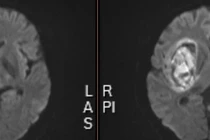

Khi ngừng thuốc trị tăng huyết áp đột ngột, huyết áp có thể tăng lên quá cao, mạch máu não không chịu nổi áp lực cao có thể bị vỡ, lúc đó bệnh nhân bị xuất huyết não, gây liệt nửa người, liệt hoàn toàn,...